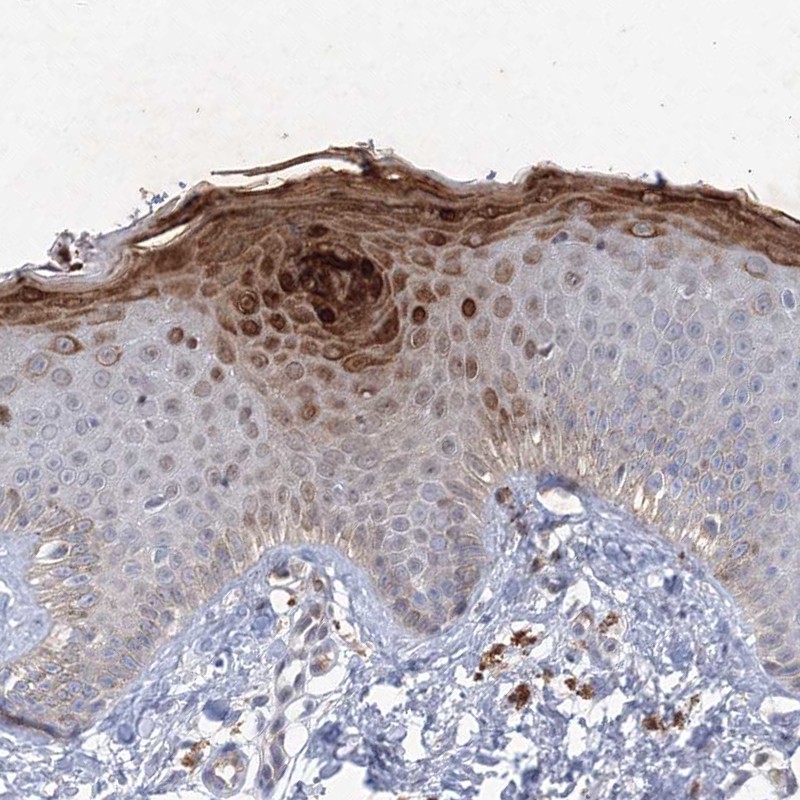

Immunohistochemical staining of human skin shows strong cytoplasmic positivity in keratinocytes.